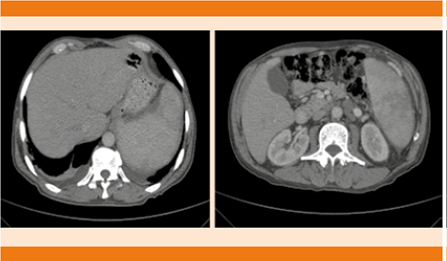

La tomografía computada de abdomen evidenció hepatoesplenomegalia, hígado homogéneo y bazo discretamente heterogéneo. En el retroperitoneo se observaron múltiples imágenes hipodensas en cadenas interaorticocavales, periaórticas en relación con actividad ganglionar (Figura 1).

Figura 1 Tomografía de abdomen que muestra hepatomegalia y esplenomegalia. Actividad ganglionar retroperitoneal.